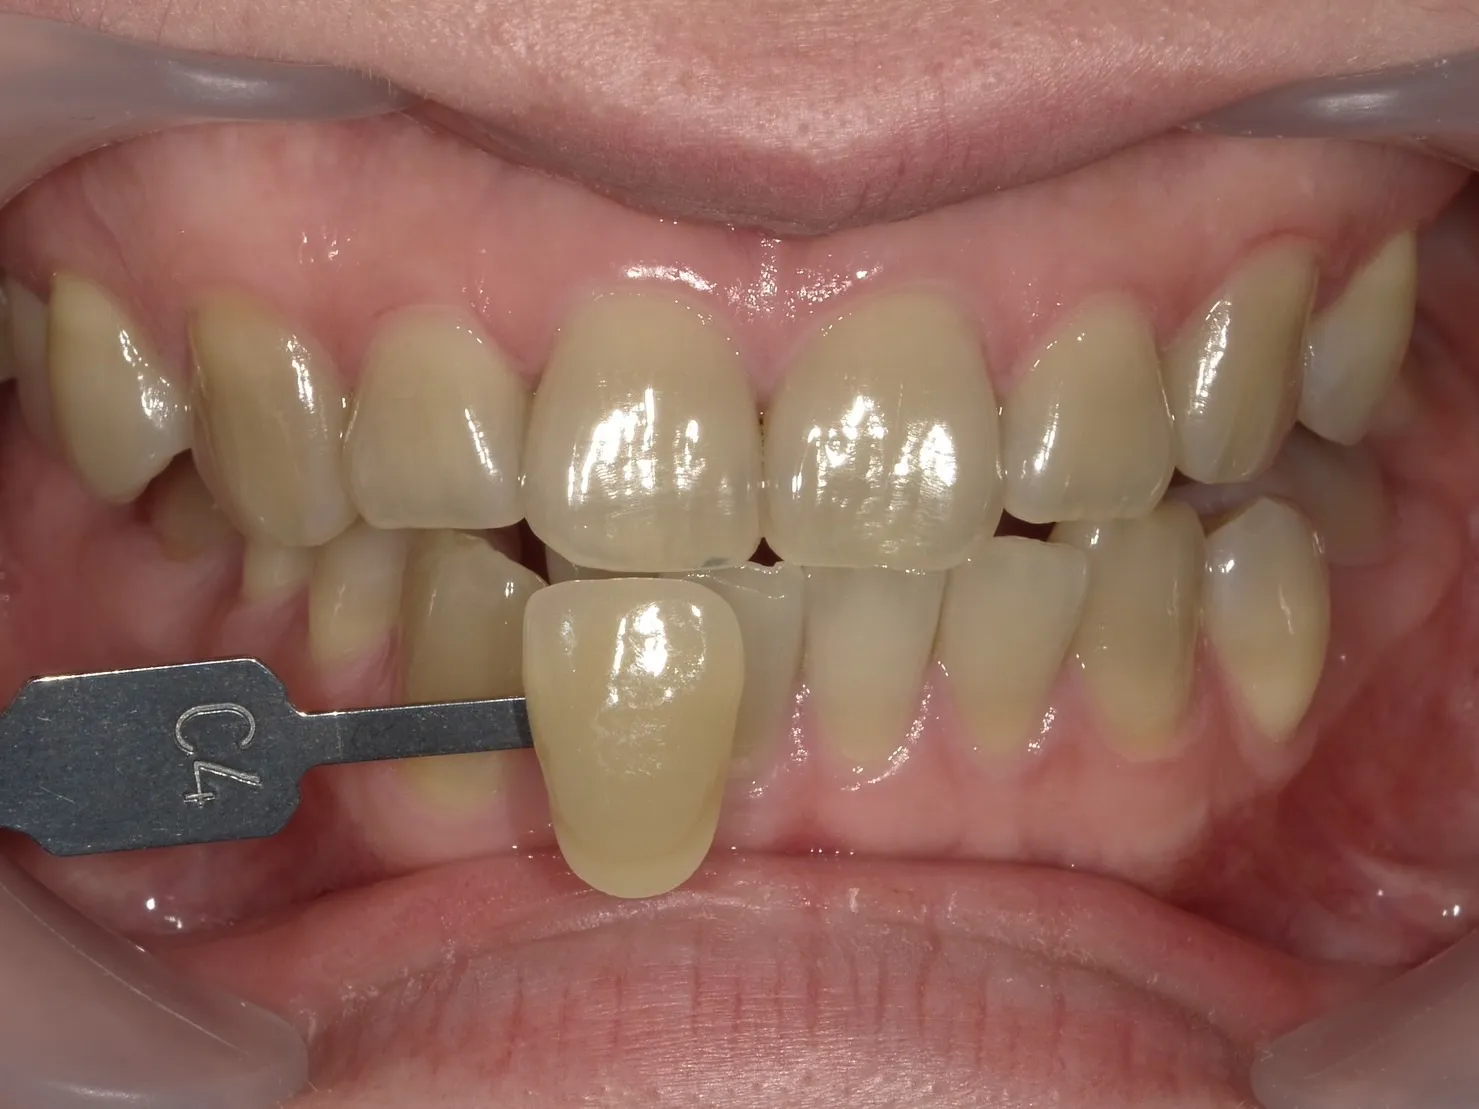

テトラサイクリン歯とは

テトラサイクリン歯とは、テトラサイクリン系抗生物質の服用によって引き起こされる歯の着色の一種です。

この状態は、特に幼少期にこの薬を服用した場合に見られることが多く、歯の発達に影響を与えることが知られています。

深い着色

テトラサイクリン歯は、黄色から茶色、時には灰色の着色を示すことがあります。

この着色は歯の表面だけでなく、内部にまで及ぶことが特徴です。

不均一な着色パターン

テトラサイクリン歯の着色は歯全体に均等に現れるわけではありません。

歯によってはバンド状、斑点状、または不規則なパターンで現れることが特徴です。